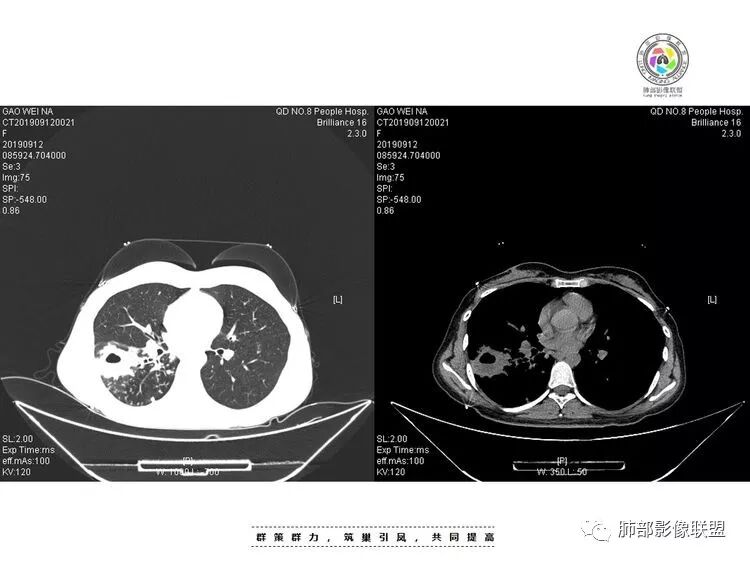

患者青年女性咳嗽、咳痰1月,加重1周,发热3天。患者1月前受凉后出现咳嗽,咳少量白色痰,1周前咳嗽加重,痰量增多,为黄白色黏痰,偶有痰中带血,轻微胸闷,近3天来出现发热,最高体温38.4℃,伴乏力,食欲下降。辅助检查:血常规白细胞及中性分类 血沉 CRP均增高。胸CT:右肺下叶前基底段实变病灶内可见空洞,洞内可见气液平面,病灶周围及右肺下叶背段可见树芽征 、结节。经抗感染治疗,基底段病灶较前缩小,背段病灶 融合 增大。考虑良性病变,空洞性肺结核合并细菌感染。

抗感染治疗后短期复查右肺病灶变化明显,部分病灶如空洞性病灶明显吸收,部分病灶稍有增大融合(如背段病灶)。

可以基本明确合并细菌感染,且变化部分不宜用结核感染解释。